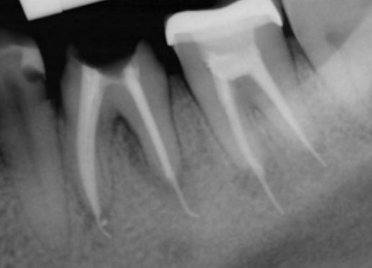

When creating your access in maxillary central incisors, what should you observe in your radiograph?

Anatomy, shape, and location of canal